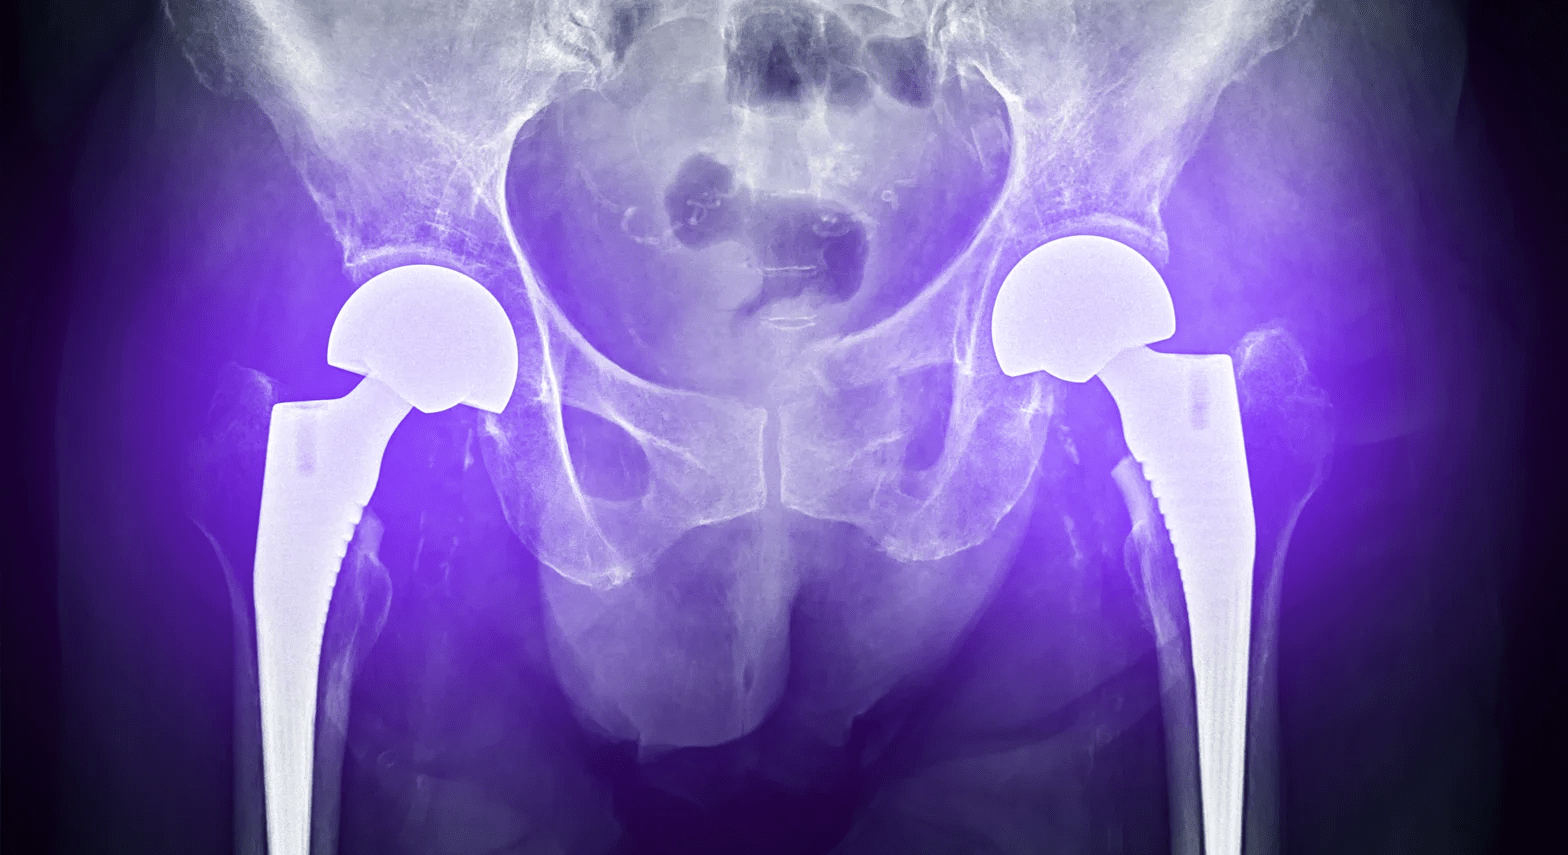

Bilateral Total Hip Replacement